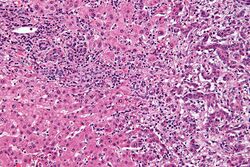

Micrograph of an intrahepatic cholangiocarcinoma (right of image) adjacent to normal liver cells (left of image). H&E stain.

Micrograph of an intrahepatic, i.e. in the liver, cholangiocarcinoma (right of image); benign hepatocytes are seen (left of image). Histologically, this is a cholangiocarcinoma as (1) atypical bile duct-like cells (left of image) extend from the tumor in an interlobular septum (the normal anatomical location of bile ducts), and (2) the tumor has the abundant desmoplastic stroma often seen in cholangiocarcinomas. A portal triad (upper-left of image) has a histologically normal bile duct. H&E stain.